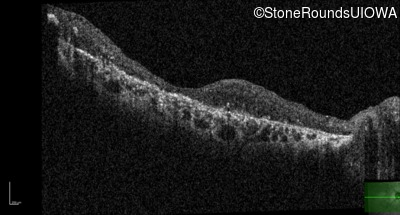

Optical Coherence Tomography - Left - 20/250 sc

Exemplar / OCT Stack